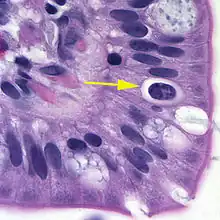

| Oocyst in epithelial cyst of mammalian host | |

The coccidian parasite Cystoisospora belli infects the epithelial cells of the small intestine, and is the least common of the three intestinal coccidia that infect humans (Toxoplasma, Cryptosporidium, and Cystoisospora).

At time of excretion, the immature oocyst usually contains one sporoblast (more rarely two). In further maturation after excretion, the sporoblast divides in two, so the oocyst now contains two sporoblasts. The sporoblasts secrete a cyst wall, thus becoming sporocysts; and the sporocysts divide twice to produce four sporozoites each. Infection occurs by ingestion of sporocyst-containing oocysts: the sporocysts excyst in the small intestine and release their sporozoites, which invade the epithelial cells and initiate schizogony. Upon rupture of the schizonts, the merozoites are released, invade new epithelial cells, and continue the cycle of asexual multiplication. Trophozoites develop into schizonts which contain multiple merozoites. After a minimum of one week, the sexual stage begins with the development of male and female gametocytes. Fertilization results in the development of oocysts that are excreted in the stool. Cystoisospora belli infects both humans and animals.

Microscopic demonstration of the large typically shaped oocysts is the basis for diagnosis. Because the oocysts may be passed in small amounts and intermittently, repeated stool examinations and concentration procedures are recommended. If stool examinations are negative, examination of duodenal specimens by biopsy or string test (Enterotest) may be needed. The oocysts can be visualized on wet mounts by microscopy with bright-field, differential interference contrast (DIC), and epifluorescence. They can also be stained by modified acid-fast stain.